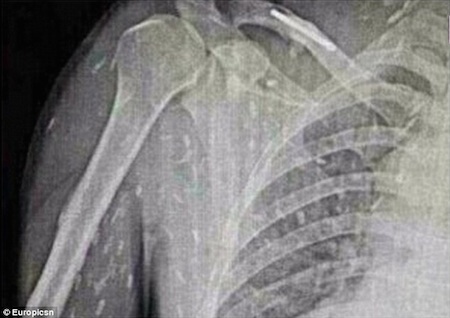

После того, как у него возникли поразительные симптомы, включая расстройство желудка и зудящую кожу, неудачный энтузиаст суши попал в больницу. В Народной больнице Гуанчжоу № 8 в провинции Гуандун он, наконец, получил лечение от заражения лейкемией. Инцидент, безусловно, один для книг, основанный на графических рентгеновских снимках ужасающей болезни. Хотя человек мог умереть от неудачного кризиса здоровья, он получил отличный уход из больницы, а затем выздоровел. Надеюсь, он в следующий раз пропустит сашими.

После того, как его отправили в больницу, выяснилось, что у него была паразитарная инфекция